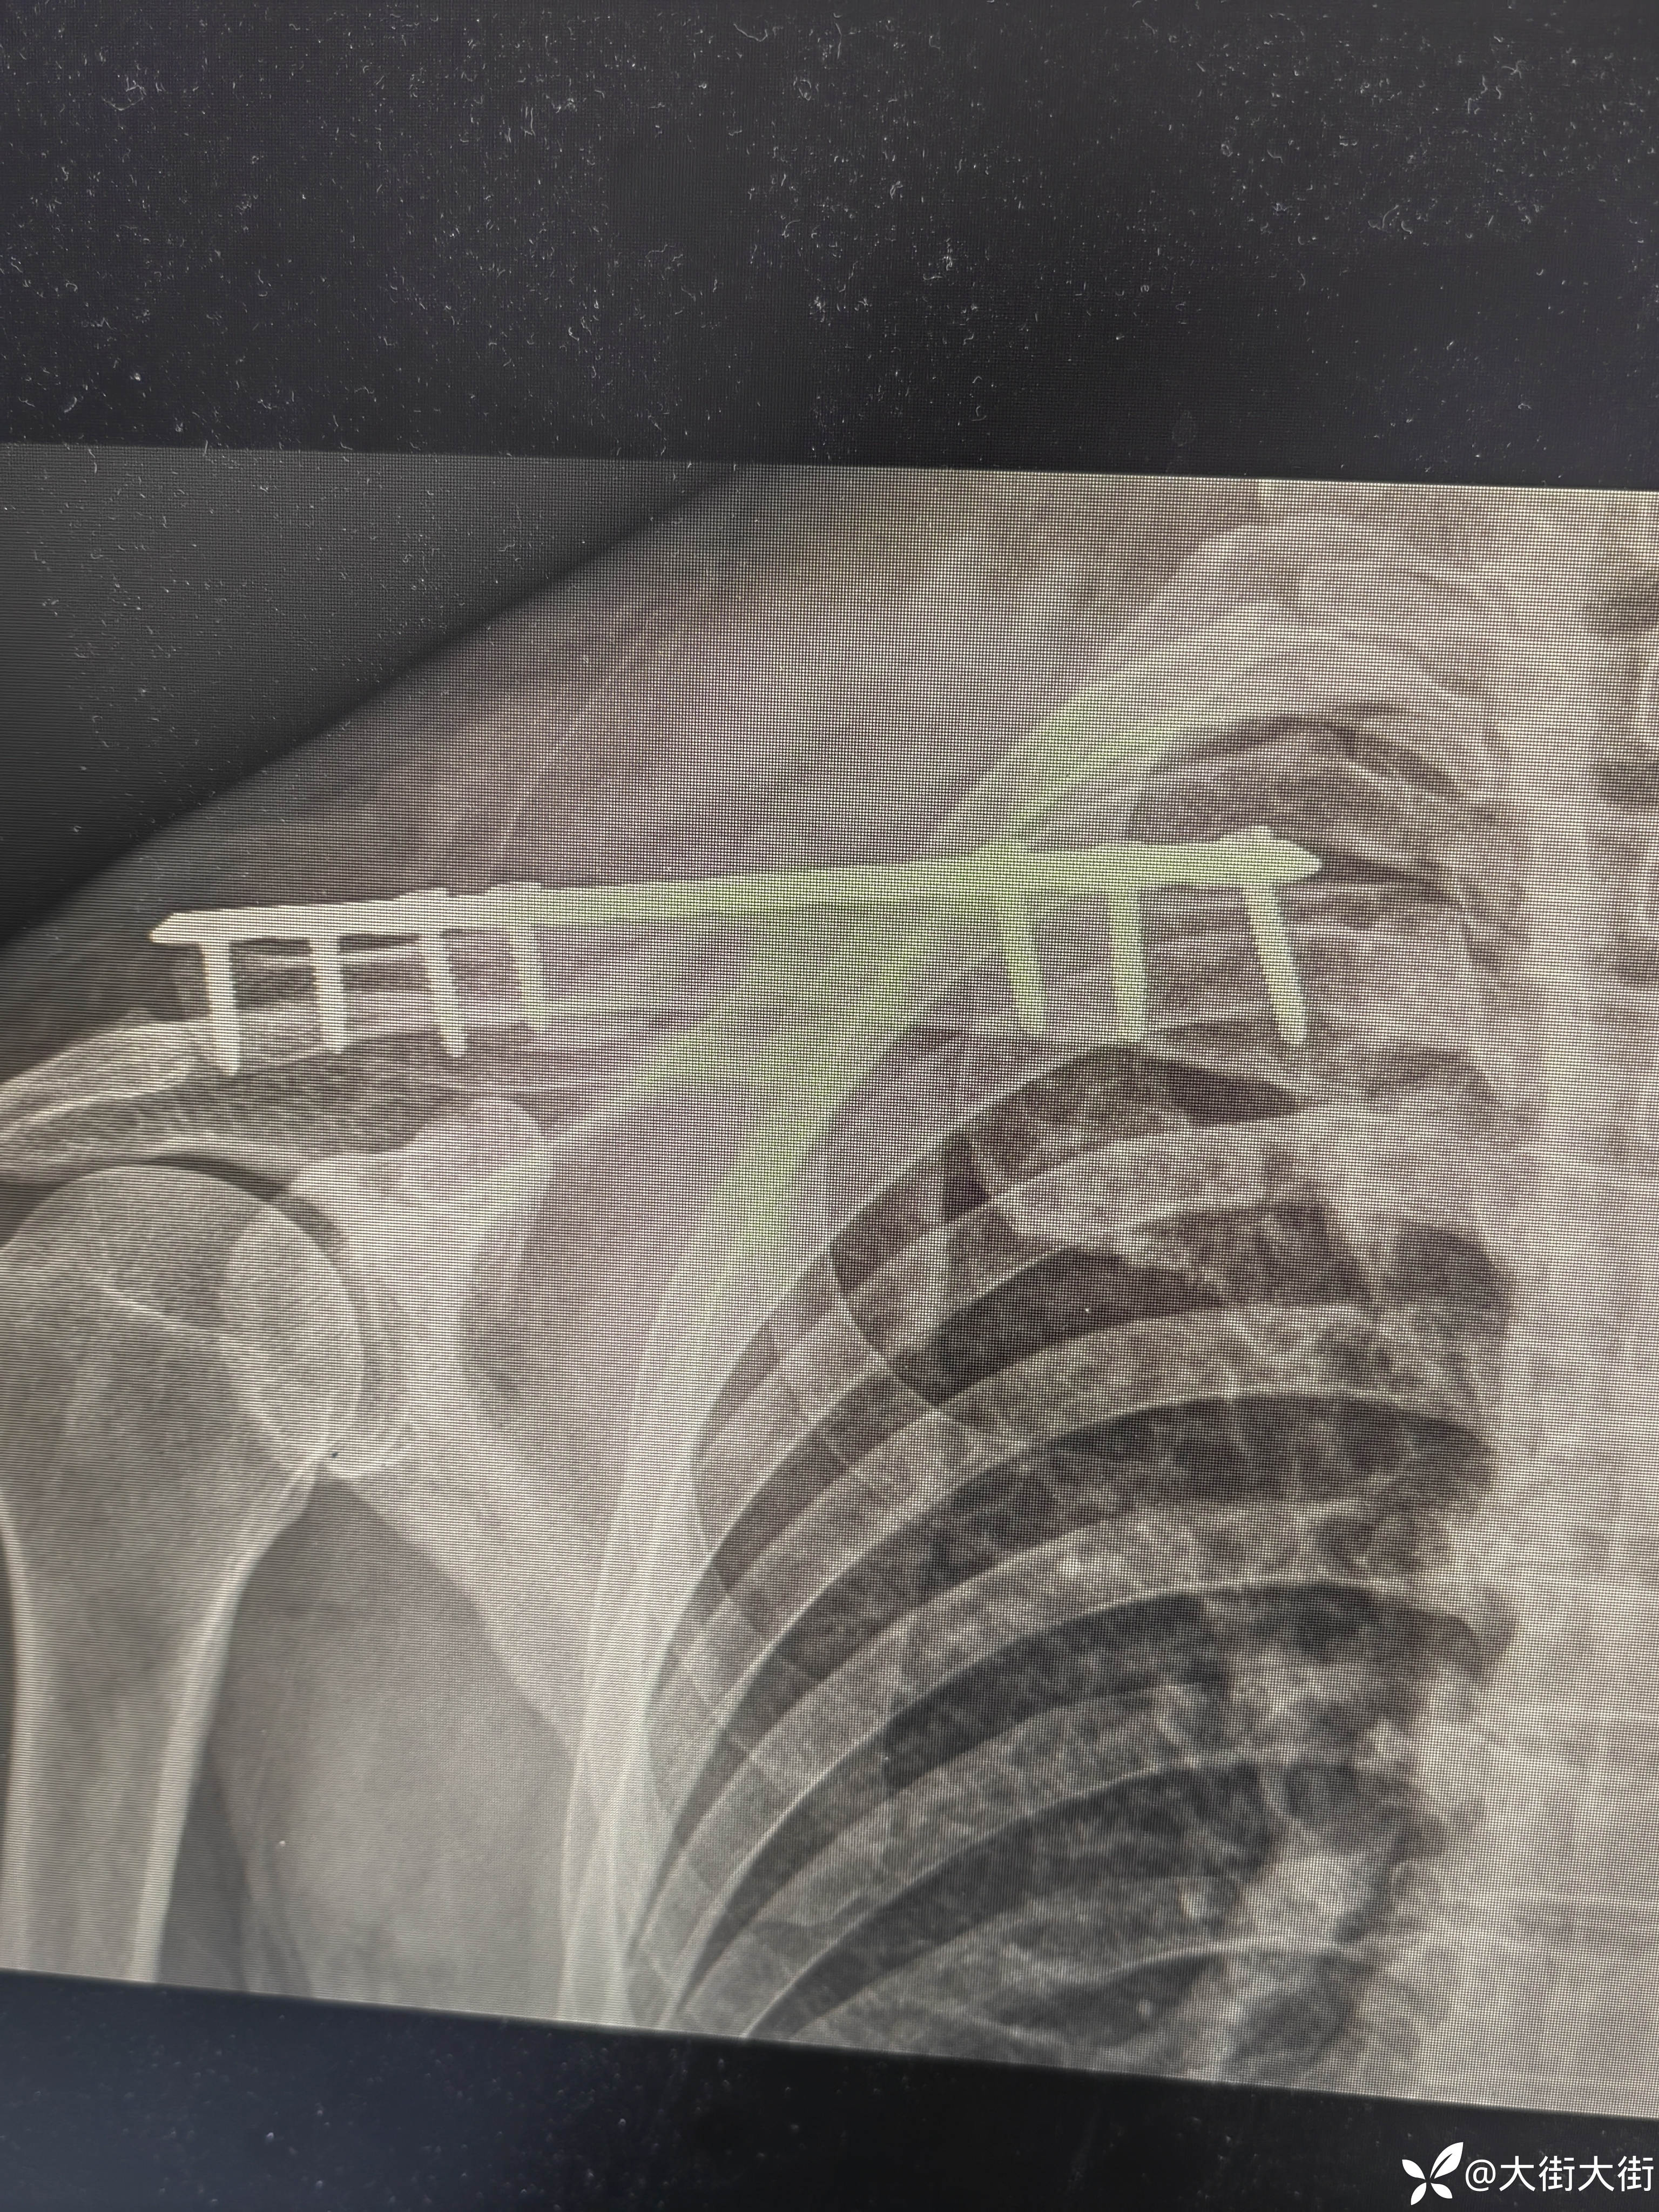

【治疗经过及结果】:

第一次做,比想象中要难点,第一感觉就是明显的视野受限。板子放的不是很完美,切口位置没把握好,下次用马克笔画一下。各位老师轻点喷。